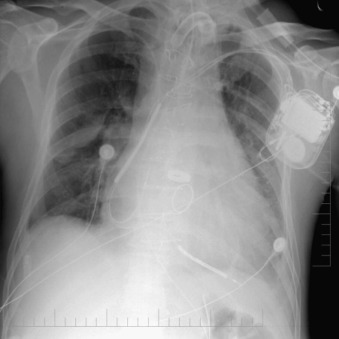

Complications of intubation ( Figs. 25-1 to 25-10 ) and ventilation that are apparent on a chest radiograph are often potentially life-threatening and should be excluded on every radiograph, both immediately following intubation and with each subsequent radiograph. These possibilities are listed in the following sections.

Esophageal Intubation

- □

Distension of esophagus and stomach with air

Location of ET tube to the side of the trachea

Cuff Overinflation

The walls of the trachea should not be distended outward by the cuff. Distension is overinflation.

Width of the ET tube two thirds of the width of the trachea